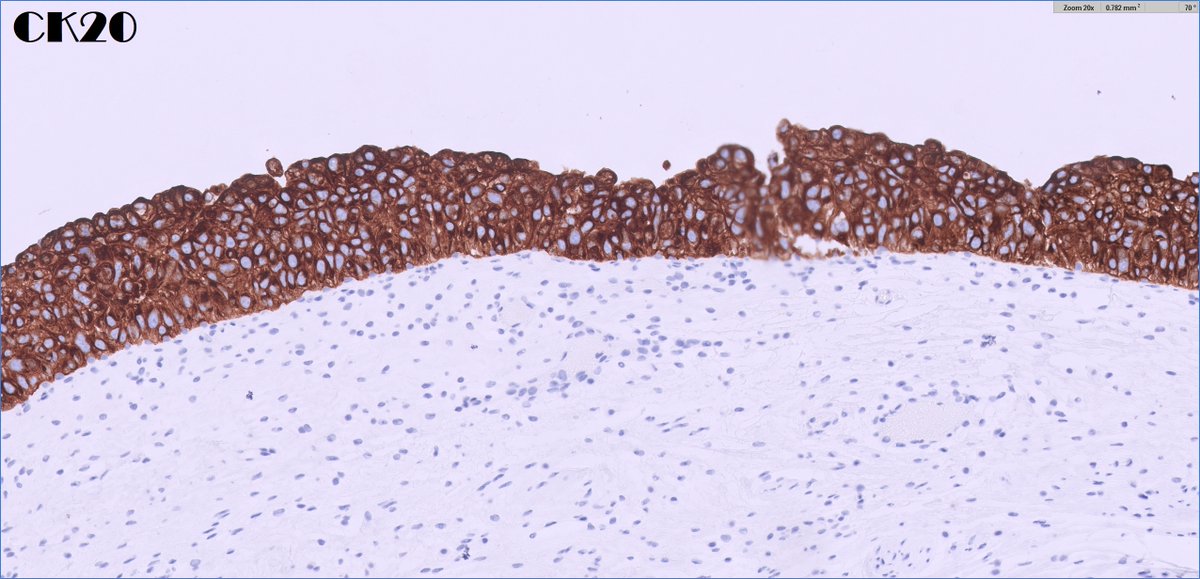

*** Case of the Month *** Bladder lesion in an 80 yr old female patient Contributors : Ronniel Morais Albuquerque Daniel Athanazio FB: GU Pathology Society IG: gu_pathology_society LinkedIN: GUPS Society Bluesky: https://t.co/1hR9PHdTaG

https://t.co/ijDfT9Juld